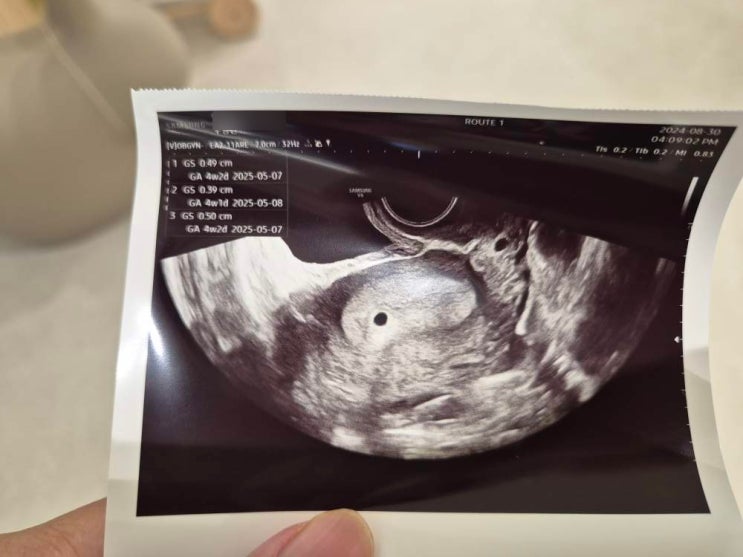

[임신 4주] 임테기 역전없이 아기집, 임신확인서 발급받기 아기집 보이는 시기 언제?

얼리테스트기로 희미한 두줄을 확인한 뒤 다음날 아침 남아있던 얼리 한번 더.. 확실히 진해졌다..! 누가 ...